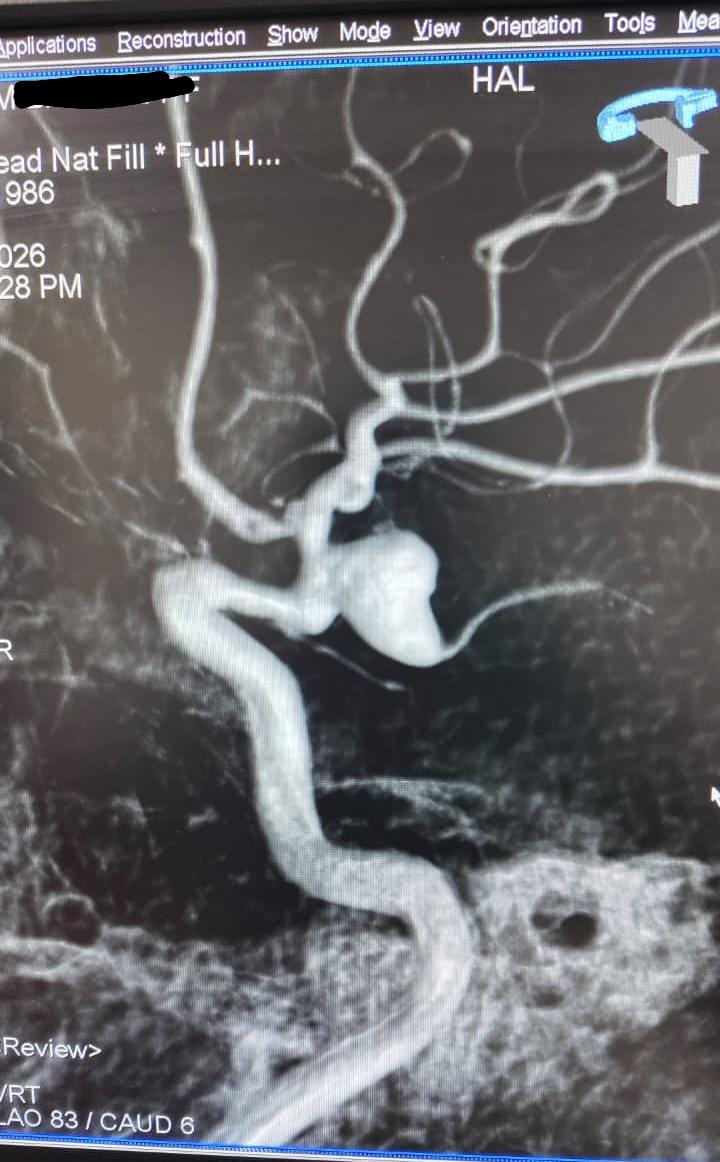

Case 4

Ruptured Brain aneurysm (left ICA communicating segment wideneck aneurysm) treated with Stent Assisted Coiling.

aneurysm cannulated with microcatheter and microwire

Coiling in live case

after complete coiling and stenting

final result complete coiling and Stenting of brain aneurysm